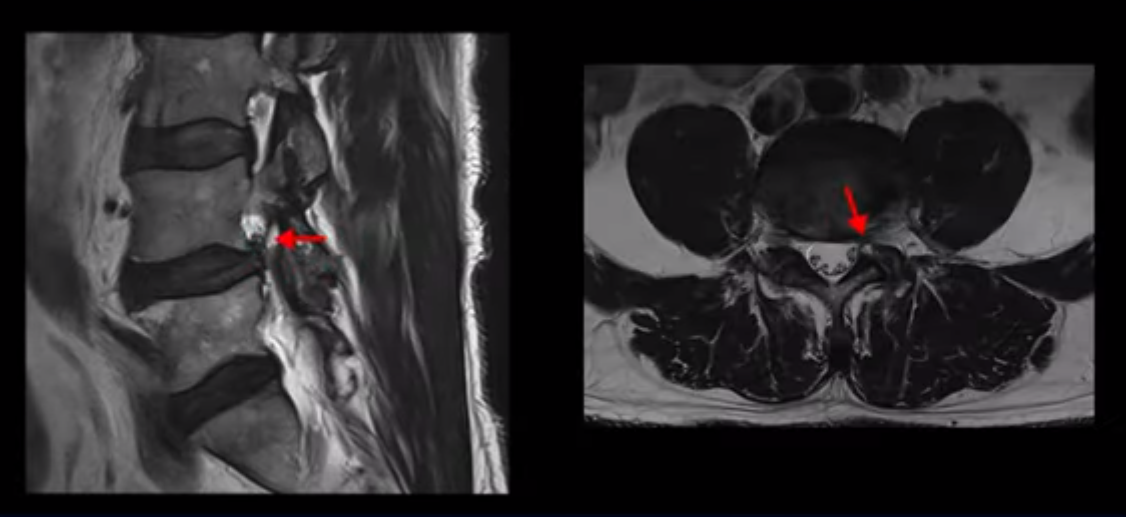

먼저 이분 MRI를 보면서 간단히 설명해 드린 후 어떻게 신경이 눌려서 수술해야 한다는 환자를 수술 없이 치료할 수 있는지, 또 어떤 병원에서는 수술할 정도로 심하지는 않다고 했는데 왜 증상은 이렇게 심한지, 그러면 수술 없이 치료는 어떻게 할 수 있는 건지 자세히 설명해 드리겠습니다.

이분 허리 MRI를 보면 60세가 넘었기 때문에 퇴행이 진행은 되었지만 아주 심하지는 않습니다.

이분 왼쪽 다리가 저리고 아파서 2~3년 전부터 걷기가 힘들었는데 이분 허리 4번, 5번 마디에 신경 가지가 빠져나가는 추간공이 다른 마디에 비해서 좁아져 있습니다. 하지만 아주 심하게 좁아져 있지는 않습니다.

의사마다 MRI를 보고 얘기가 달랐다고 하는데 심하지 않다고 하는 쪽이 맞습니다. 그런데 이분은 신경 구멍 넓이에 비해 증상은 매우 심한 편입니다. 왜 그럴까요? 이 이유와 어떻게 치료하는지에 대해 지금부터 설명해 드립니다.